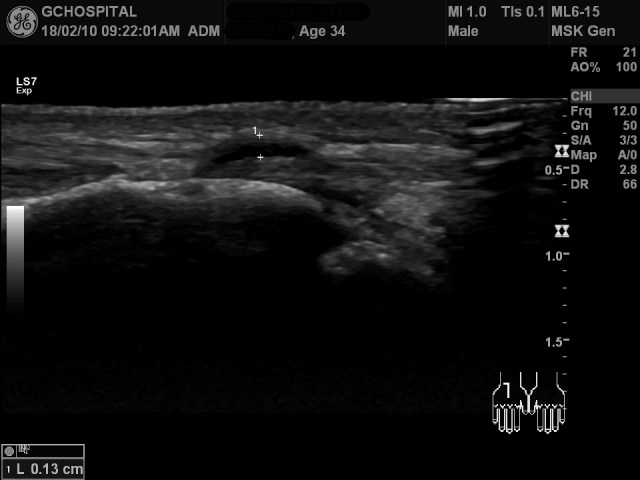

힘줄과 같은 방향으로 탐촉자를 위치해서 얻은 영상에서 낭종성 병변이 힘줄을 둘러싸고 있습니다. 영상에서는 또렷하지 않지만, 위 영상에서도 낭성병변은 더 깊이 들어가면서 carphometacarpal joint space와 연결이 되어 있었습니다.